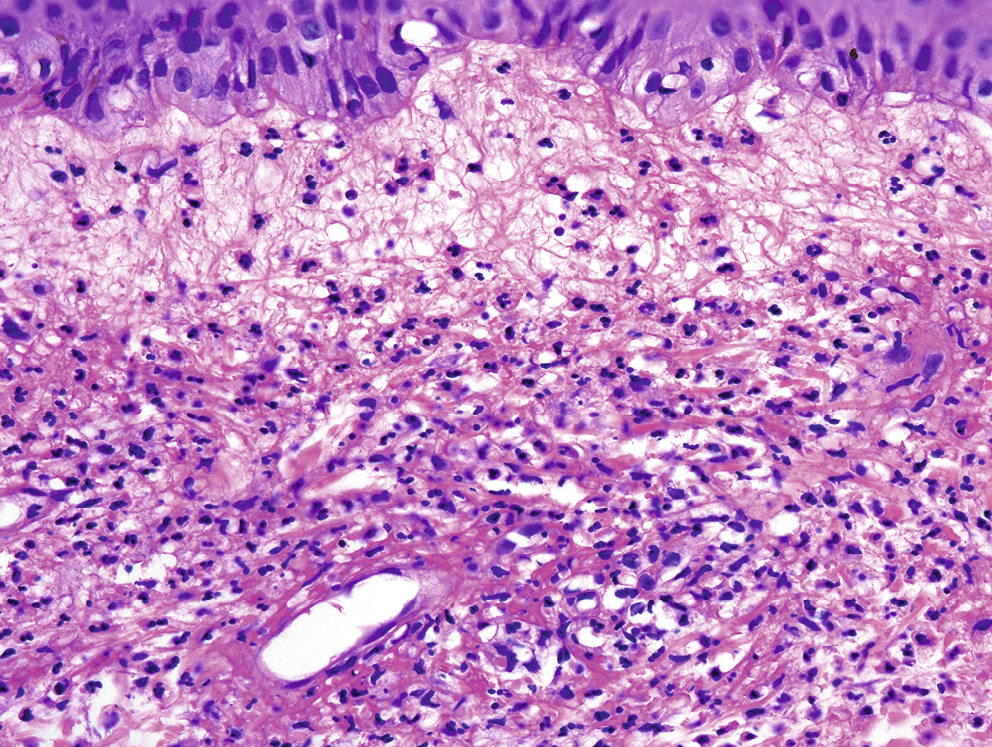

Эритема возвышающаяся стойкая — это нейтрофильный дерматоз (классифицируется как поражение дермы с васкулитом), при котором отмечается хронический локализованный фиброзирующий лейкоцитокластический васкулит. Изменения в коже начинаются с поражения посткапиллярных венул (отложения фибрина в стенках сосудов, лейкоцитоклазия), в стенках часто обнаруживаются депозиты из иммунных комплексов. Периваскулярные инфильтраты смешанные, включают нейтрофильные гранулоциты (присутствуют всегда), гистиоциты, плазматические клетки и эозинофильные лейкоциты (рис. 5). На ранних стадиях развивается выраженный отек сосочковой дермы, который клинически иногда ошибочно расценивается как везикуляция. Позже в периваскулярных инфильтратах увеличивается количество гистиоцитов, отмечается пролиферация веретенообразных клеток, развивается фиброз [31, 32].

Рис. 5. Эритема возвышающаяся стойкая. Инфильтрация дермы нейтрофильными лейкоцитами. Лейкоцитокластический васкулит сосудов малого калибра

Fig. 5. Erythema elevatum diutinum. Infiltration of the dermis with neutrophilic leucocytes. Leukocytoclastic vasculitis of small-caliber vessels